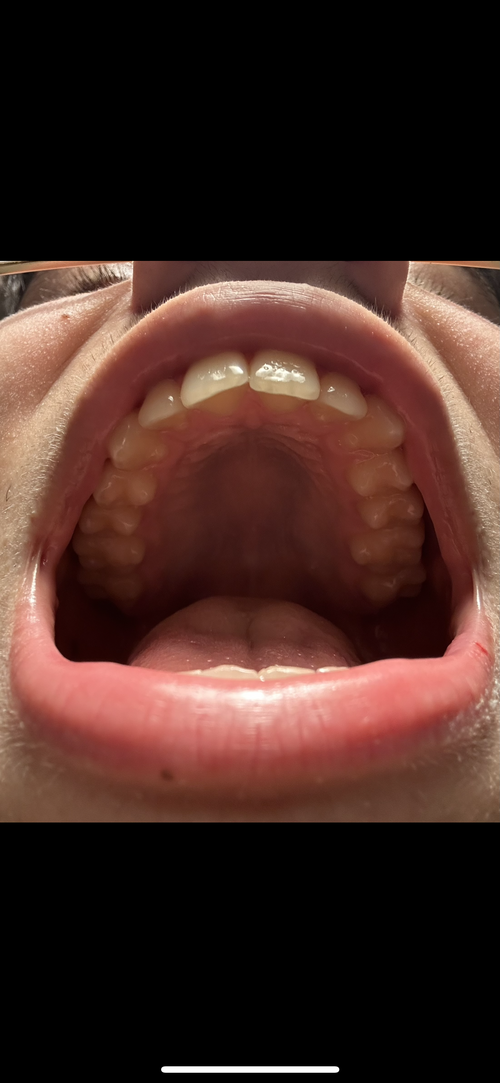

My palate doesnt seem narrow people told me before it wasnt but i just feel like my smile is so weird ahh and i never smile in pictures irl ok but in pictures no.

I feel like my back teeth should show more idk just wanna make sure i dont need it so i dont need to worry about it.

I did expand with a palatal expander in the first picture u can see my right back teeth showing but they went back idk how

I feel like my back teeth should show more idk just wanna make sure i dont need it so i dont need to worry about it.

I did expand with a palatal expander in the first picture u can see my right back teeth showing but they went back idk how